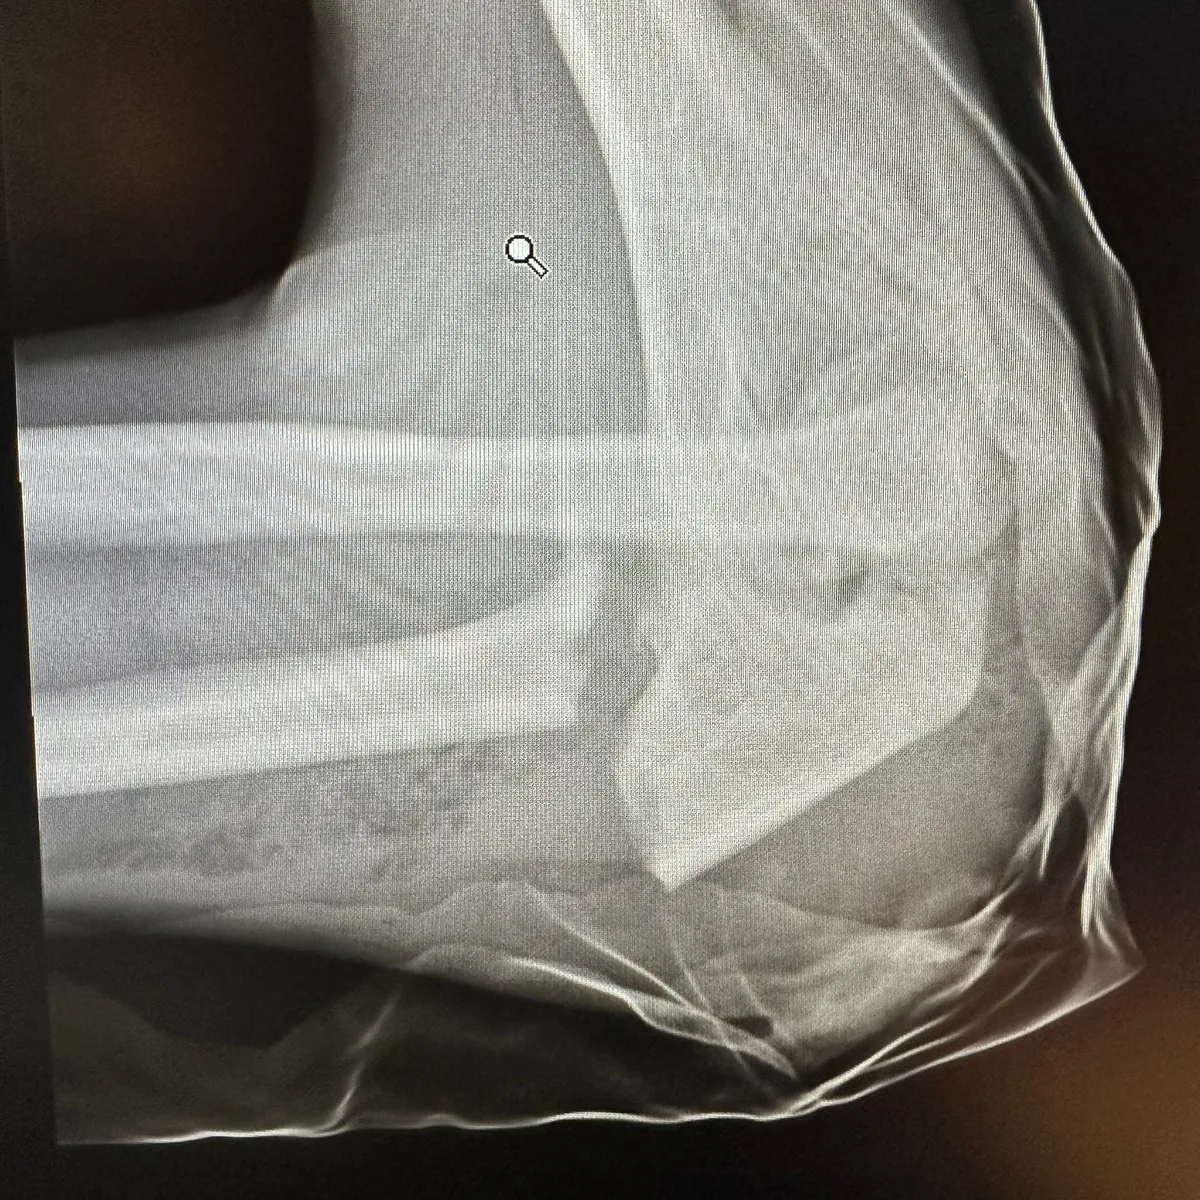

Egyetlen hirtelen fékezés is elég lehet ahhoz, hogy komoly sérüléssel végződjön egy rollerezés. Erre hívja fel a figyelmet a Sebészek a Gyermekekért Alapítvány a legutóbbi posztjában. Egy 16 éves fiú ugyanis egy átlagos tempójú, körülbelül 25 km/h-s haladás közben bukott át az elektromos rollerének kormányán, és olyan súlyos könyöktörést szenvedett, hogy műtéti beavatkozásra volt szüksége.

A fiatal szabályosan, körülbelül 25 km/h-s sebességgel közlekedett elektromos rollerével, amikor egy hirtelen fékezésnél átrepült a kormány felett. Ugyan viselt bukósisakot és kesztyűt, és egyedül használta a rollert, mégsem tudta elkerülni a balesetet.

Azon tudunk változtatni, hogy amikor ilyen baleseti szituáció van, akkor mi védi meg a szervezetünket. A fiú könyöktörést szenvedett, de mivel 25 km/h-val ment, viselt bukósisakot, egyedül használta a rollert és vélhetően szabályosan közlekedett, más komoly sérülése nem történt.